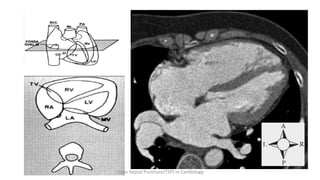

IAS plane in supine patient

From 2’ to 7’ o clock

Trans Septal Puncture(TSP) in Cardiology